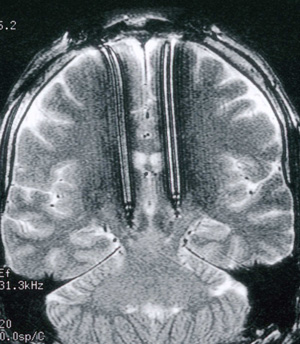

Fourteen patients (nine men) underwent bilateral electrode implantation into the subthalamic nucleus. Their median age was 59 years (range, 36–74 years) and median disease duration was 13 years (range, 3–33 years). Median presurgical disability on the motor exam component of the UPDRS5 was 28 (range, 8–55) without medication and decreased to a median of 13 (range, 2–25) with medication (Box 2).

After surgery, stimulator leads were explanted in one patient (Patient 12) and relocated to the thalamus in a second (Patient 13; Box 3). Patients 11 and 14 did not attend the six-month evaluation because of extraneous factors, leaving follow-up data for 10 patients. Despite considerable variation between patients, motor exam results showed that motor performance with no treatment was significantly worse at six months after surgery (Box 4a; t(9)  = 2.343; P = 0.044) and medication effectiveness tended to diminish over the same period. At six months, stimulation alone was as effective at improving motor performance (t(9) = 5.952; P < 0.001) as medication (t(9) = 4.035; P = 0.003), and combining stimulation and medication further reduced motor difficulties (t(9) = 4.291; P = 0.002). Motor performance improved despite overall reduced levels of medication (Box 5), and was thus accompanied by fewer levodopa side effects such as dyskinesias. This effect did not reach significance owing to several subjects without presenting dyskinesia.

There was marked variability in response to deep brain stimulation among our patients. Although some of this resulted from the difficulties noted above, further variability may have related either to the stimulators themselves or their positioning. Electrode positioning may have been suboptimal, as we did not have single-cell recording equipment to pinpoint subthalamic cells. The quadripolar electrodes used have a larger interelectrode distance than those used elsewhere. By allowing better localisation of the deep brain stimulation effect, closer electrode spacing may reduce overflow to proximal structures, enabling better symptom control without side-effects. These differences, combined with an older sample size, may explain why medication reductions were smaller and parameters such as gait improved less in our study than in some others.19,21 Our failure to show improved postural stability with stimulation is not unexpected given its failure to improve with levodopa medication.22